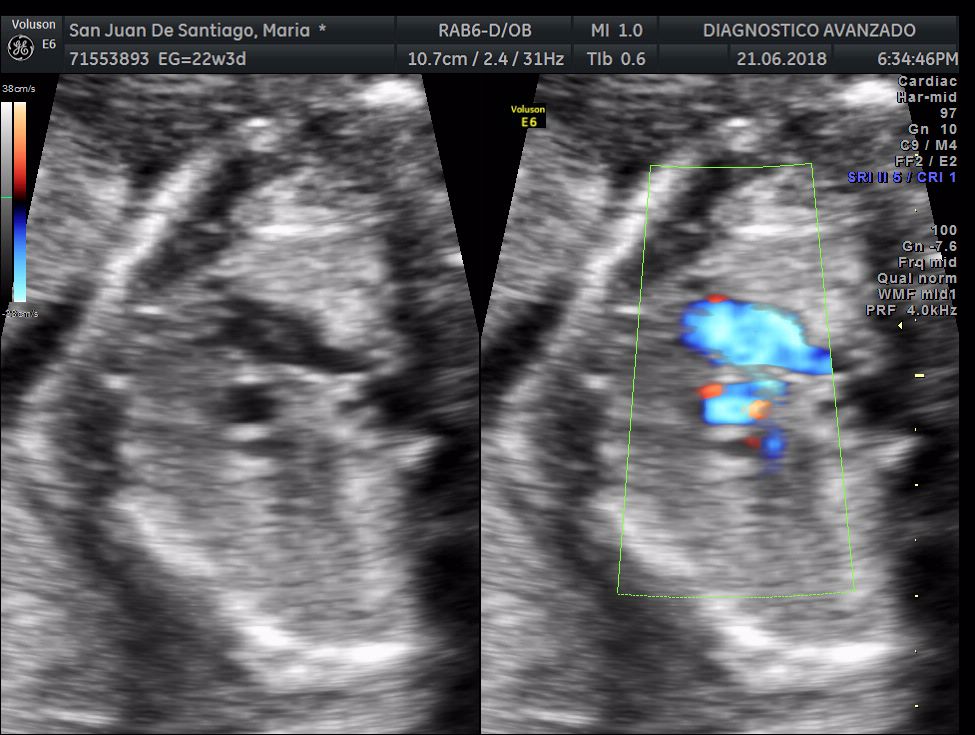

¡Hola a todos! Hoy hemos ido a hacer la tradicional ecografía 3D de la niña, os dejamos todo el material (aunque es un poco demasiado).